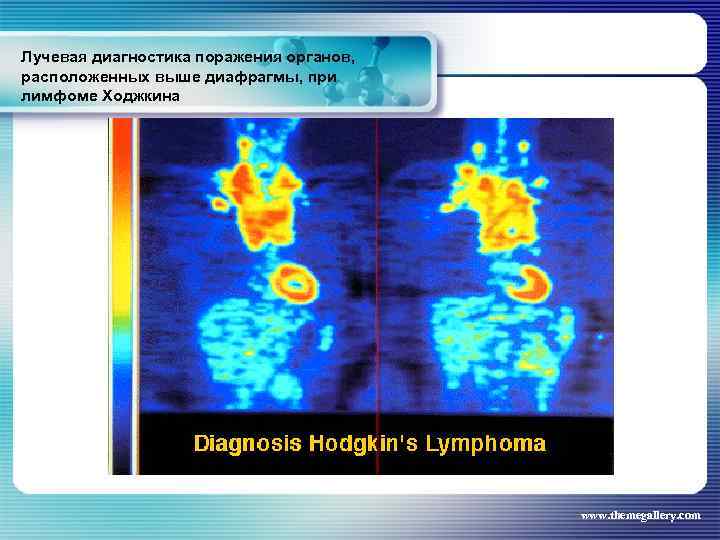

Лучевая диагностика поражения органов, расположенных выше диафрагмы, при лимфоме Ходжкина Частота поражения органов грудной полости при лимфоме Ходжкина: поражение средостения легких плевры грудной стенки - 66, 7 % 33, 75% 5, 3% 1, 8% www. themegallery. com

Лучевая диагностика поражения органов, расположенных выше диафрагмы, при лимфоме Ходжкина Частота поражения органов грудной полости при лимфоме Ходжкина: поражение средостения легких плевры грудной стенки - 66, 7 % 33, 75% 5, 3% 1, 8% www. themegallery. com